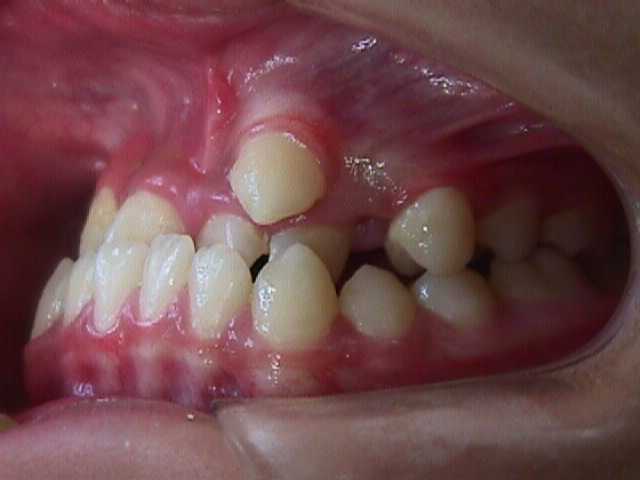

【矯正症例】左上2番3番逆転症例2

左上2番3番逆転症例

随分、前の症例で現在、写真しか残っておりません。

治療費や、治療期間を掲載できないことをご了承ください。

私の矯正歯科医の人生の中でも、特に思い出深い症例です。